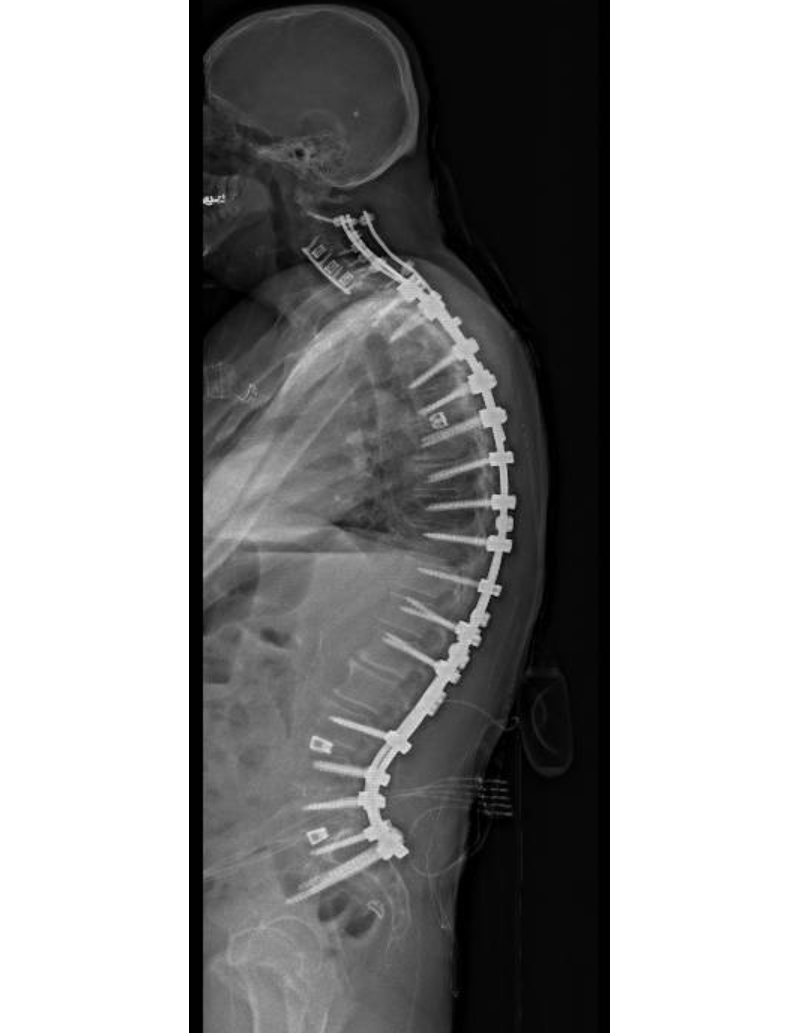

Preoperative x-ray of patient's spine

Preoperative lateral X-rays showing the hyperkyphosis of the thoracic spine and the kyphosis of cervical spine making it difficult for the patient to hold heir head up.